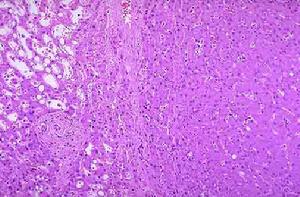

2.病理改變 肝腺瘤病理上分為肝細胞腺瘤膽管細胞腺瘤(包括膽管腺瘤及膽管囊腺瘤)混合腺瘤。肝細胞腺瘤多見於右葉(67%),70%為單個結節,直徑一般大於10cm最大可達20~30cm。偶爾腫瘤可呈多個結節腫瘤邊界清楚常有不完整的纖維包膜切面上腫瘤稍隆起質地與周圍肝組織相近但顏色稍淺,可見出血和梗死。鏡下腫瘤細胞呈索狀排列細胞索由1~2排肝細胞組成這些細胞較正常肝細胞稍肥大但異型性不明顯,核分裂象偶見或缺乏。偶見細胞異型性,這種情況常見於長期使用同化類固醇或口服避孕藥者有時瘤細胞排列成腺管狀管腔見膽栓瘤內常見擴張呈囊狀的血竇當出現大量囊狀血竇時形成肝紫癜症。

瘤細胞臨床表現隨腫瘤大小、部位及有無併發症而不同。5%~10%無任何症狀,系查體或手術時偶然發現。約1/3的肝腺瘤病人有腹塊及近期發生的右上腹疼痛性質可為隱痛,並有噁心納差等不適;但當腫瘤發生破裂出血時,病人可出現突發的右上腹劇痛,查體可發現腹肌緊張局部壓痛反跳痛,嚴重者病人可有失血性休克的表現;黃疸及發熱偶見應引起臨床工作者注意的是HCA不僅有破裂出血的傾向而且還有惡變為肝細胞肝癌的潛能。早期可無任何症狀,待腫瘤長大到一定程度時,才會出現下列臨床徵象: